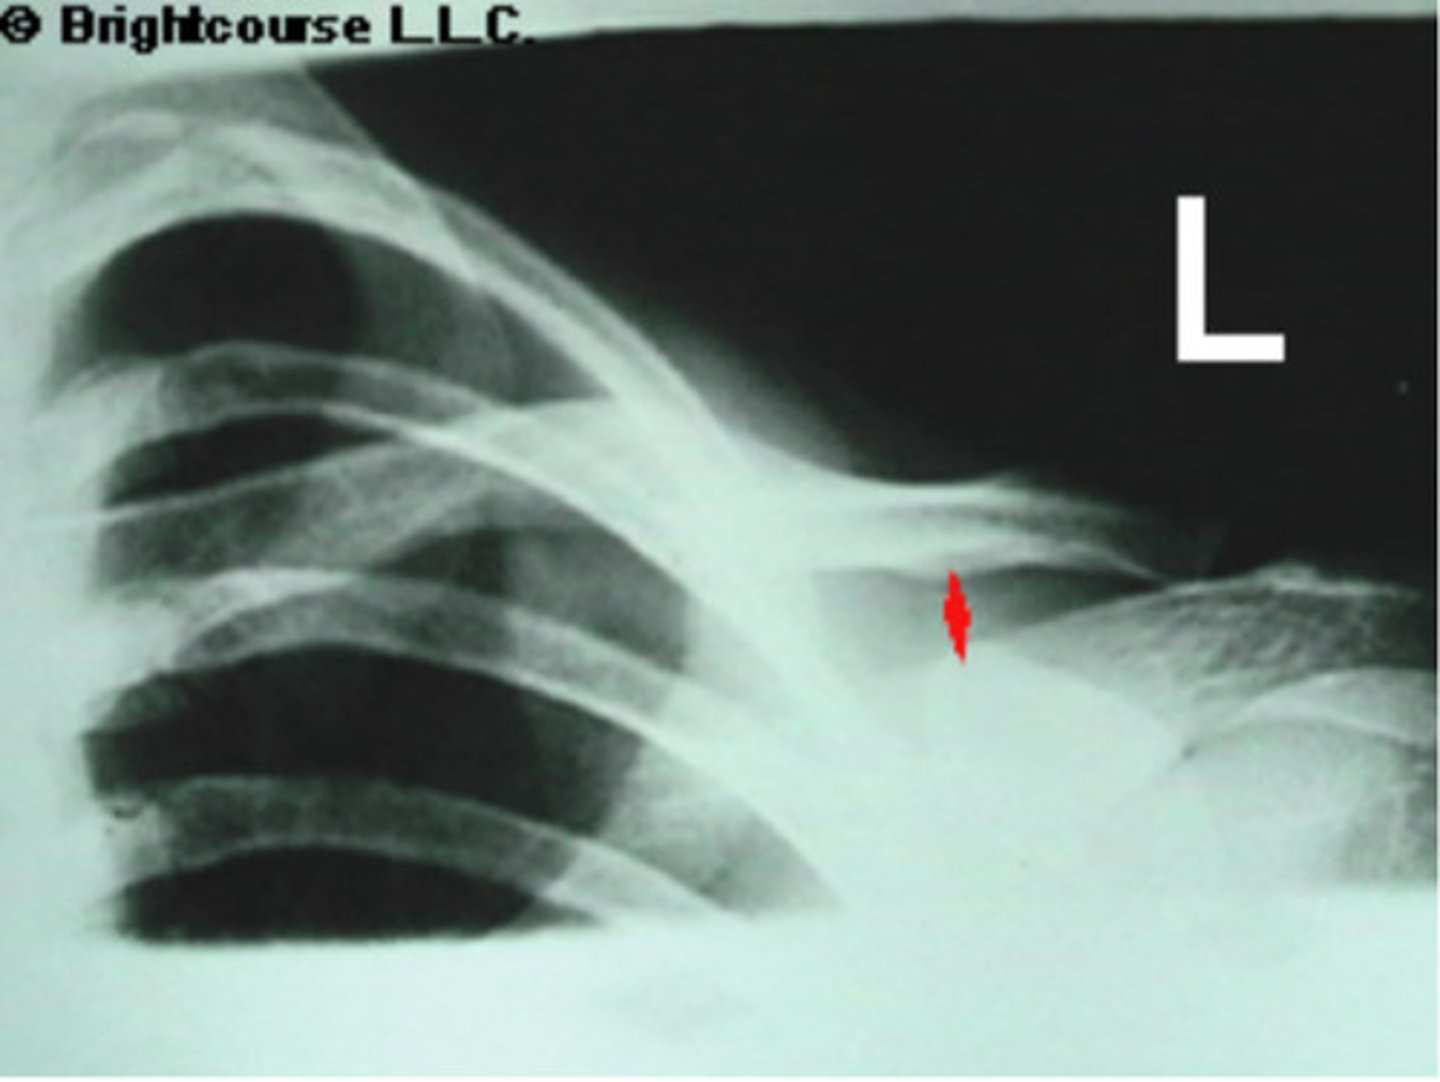

Proximal shaft of humerus

What is being pointed out by the arrows in the image?